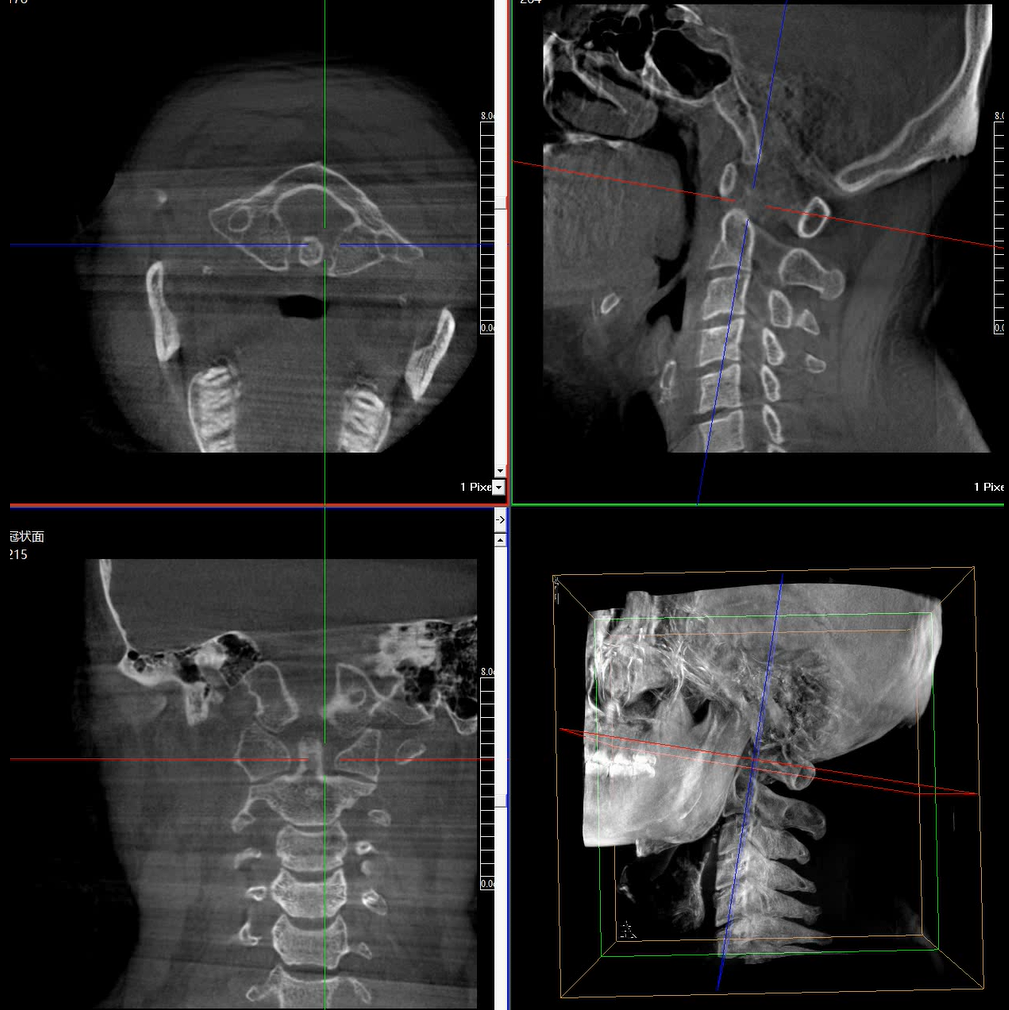

術(shù)中三維成像和橫斷面圖像提供多角度的手術(shù)診斷信息,輔助醫(yī)生進(jìn)行術(shù)中評(píng)估判斷,諸如骨折復(fù)位情況和內(nèi)植入螺釘?shù)某叽绾臀恢茫o助手術(shù)更好地完成。

提供更大的術(shù)中三維成像視野,采集更多圖像信息,可一次拍全全段頸椎、全段腰椎、七節(jié)胸椎、雙側(cè)骶髂關(guān)節(jié)、股骨頭及單側(cè)盆骨。

在C臂掃描過程中,始終保持拍攝主體處于射線束的中心,避免了序列圖像采集過程中的橫縱方向運(yùn)動(dòng),減少相對(duì)運(yùn)動(dòng)造成的運(yùn)動(dòng)偽影。